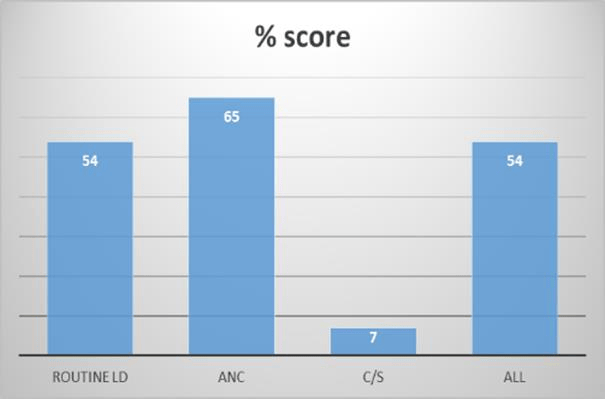

Quality of Basic Maternal and Neonatal Care Signal Function and Clients Perceived Care in Health Facilities in Malawi: An Analysis of the National Health Services Survey Using 2013-2014 Malawi SPA Survey Data

Background: Maternal and neonatal healthcare is a critical component of overall health services, and its quality profoundly influences health outcomes....Read More